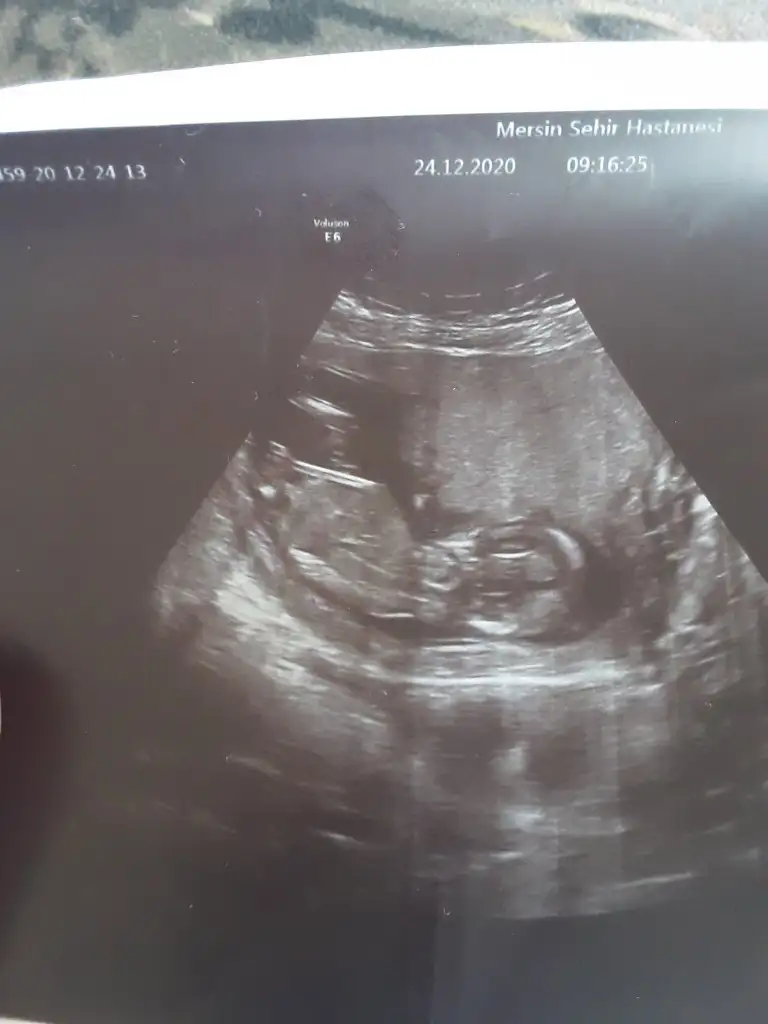

Erkek görünüyorMerhaba kızlar, 12+3 haftalığız bugünki ultrason görüntümüz. Doktorumuz bir tahmin yaptı bakalım sizce nedir cinsiyeti?

Eki Görüntüle 2749290 Eki Görüntüle 2749292

Çok net değil USG kız diyecem ama emin değilimBiz de bugün 12+0 çıktık ultrasonda doktor yüzde 60lık bir tahmin yaptı ama size de sormak istedim :)Ikra meyra